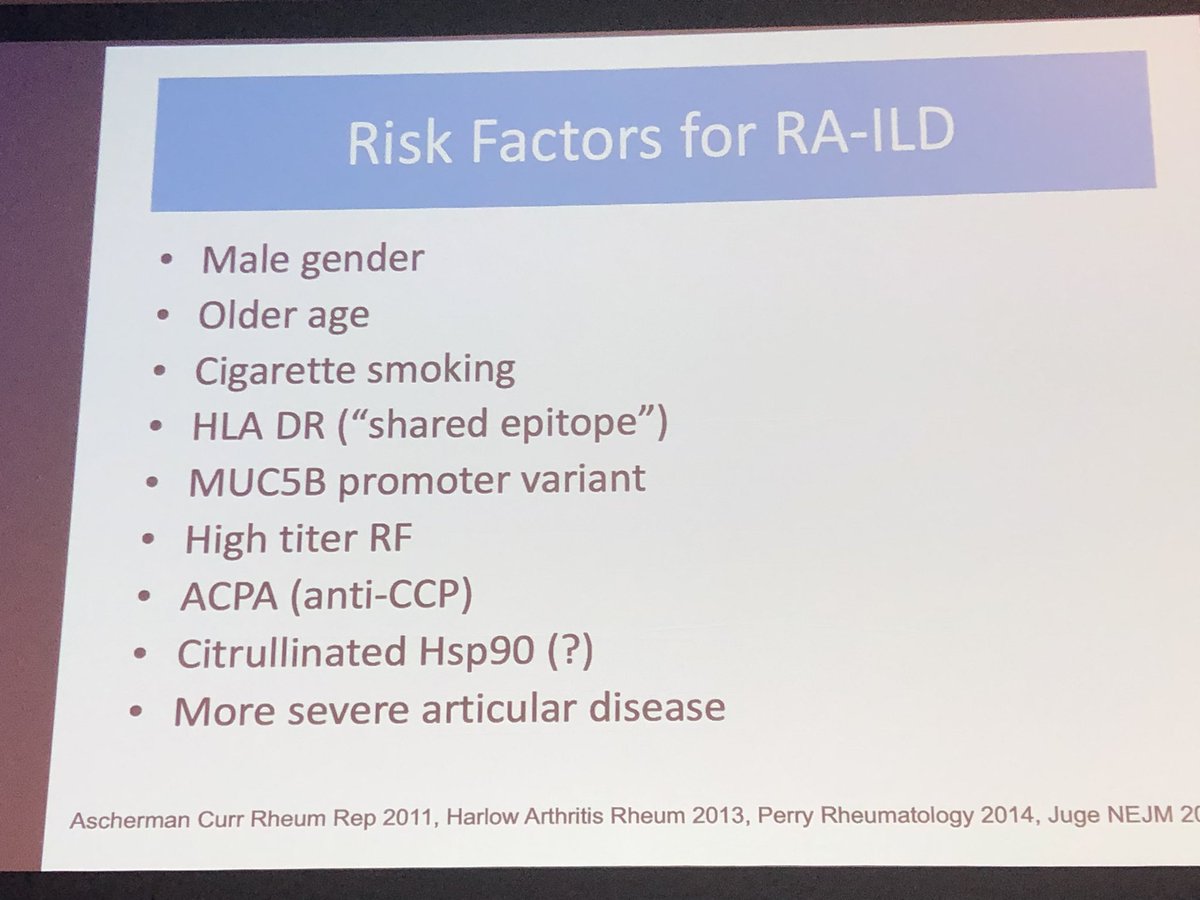

PHAROS is a prospective cohort studying the natural history of pulmonary hypertension (PH) in systemic sclerosis (SSc). They have shown that risk factors for poor outcomes in this cohort included male sex, DLCO < 50%, exercise oxygen desaturation, and pericardial effusions.